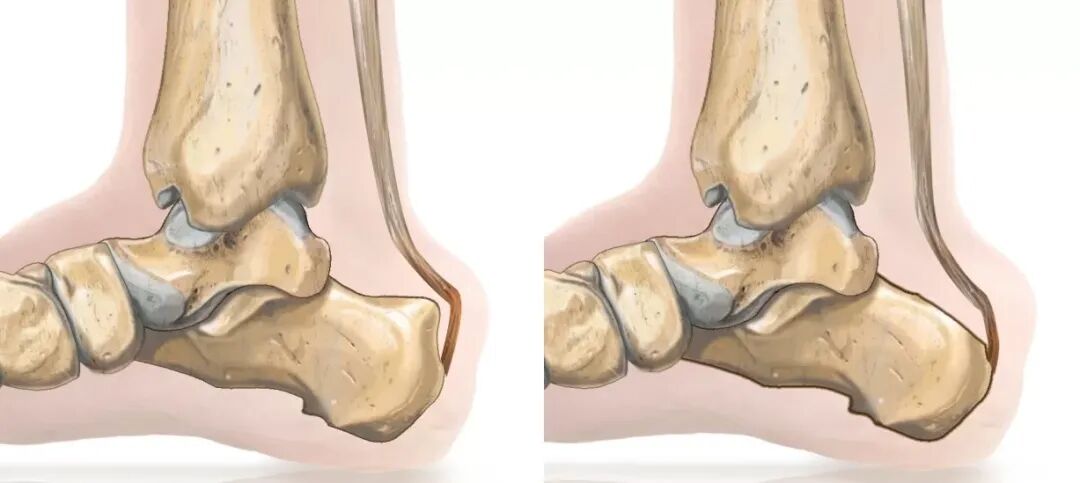

跟腱慢性过度负荷加上外部压力会导致骨肥大和伴随的滑囊炎,这反过来又会促进跟腱止点腱病的发生。因此,跑步者的反复负荷在跟腱止点腱病的发展中起着重要作用。跟骨后上外侧突起以及伴随的跟腱止点腱病被称为 Haglund 综合征或Haglund畸形。

Haglund畸形的手术治疗包括切除跟骨背外侧部分、发炎的滑囊以及跟骨后区域直至跟腱附着点的退行性变的肌腱部分。总体而言,手术有望取得良好的临床效果和较高的主观满意度。与开放技术相比,内镜手术可获得更好的AOFAS评分、更低的并发症发生率和更短的恢复时间。

本文描述了微创、内镜辅助下切除Haglund畸形的技术。通过2个跟腱旁切口,在内镜辅助下切除突出的骨赘。手术目标是消除骨性撞击以及软组织对其的疼痛反应。

标记解剖标志:跟腱(虚线)、腓肠神经(S)。腓肠神经走行于腓肠肌两头之间,向尾侧位于跟腱外侧。注射针(红色星号)用于确定跟腱外侧骨赘与跟腱之间的正确皮肤切口。

在透视控制下用套管针标记关节镜和切除器械的进入点。此处显示可良好到达Haglund骨赘。